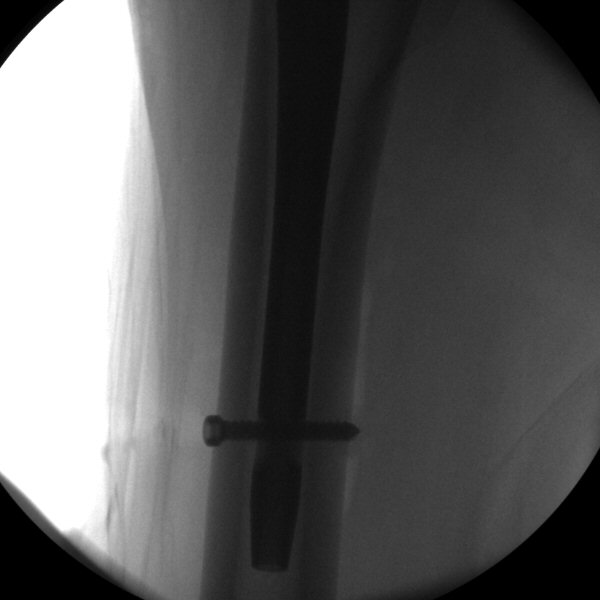

- För in låsskruvsguiden ända in till benet, tryck hårt så den går igenom fascian, lås fast genom att skruva på "Target Sleeve Knob", borra i genomlysning, tryck först mycket försiktigt mot första kortex så borret gör ett märke i kortex, sedan kan man trycka hårdare. Borra igenom båda kortex, borren ska inte träffa spiken.

- Mät med mätsticka hur lång skruv som behövs, avrunda uppåt.

- Skruva in låsskruven, kontrollera läget med genomlysning, den ska gå genom båda kortex.